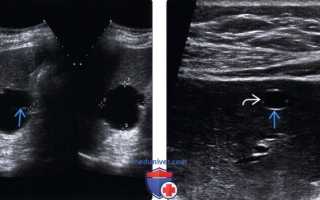

Среди специальных методов диагностики безусловное преимущество имеет ультразвуковое исследование. Его диагностическая точность колеблется в пределах 90—100%. Метод позволяет выявлять кисты диаметром более 5 мм. Он прост, доступен и неинвазивен. Непаразитарные кисты печени определяются как округлые образования с четкой капсулой, хорошо пропускающей ультразвуковые волны.

УЗИ. Киста печени

УЗИ. Описторхозные кисты печени

Кисты печени необходимо дифференцировать с паразитарными кистами при эхинококкозе и описторхозе, большими полостями распада при альвеококкозе и раке печени. При паразитарных кистах характерна ультразвуковая и рентгенологическая картина (обызвествление капсулы, наличие дочерних пузырей, характерные изменения желчевыводящих протоков при описторхозной инвазии), а также иммунологические реакции.